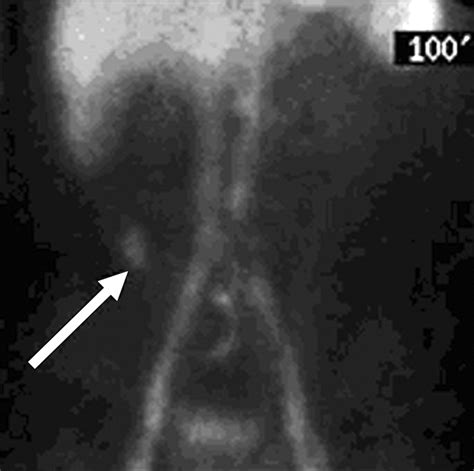

A Meckel’s Diverticulum Scan utilizes a radioactive tracer, typically Technetium-99m pertechnetate. This tracer is absorbed by the gastric mucosa cells, making them visible under a specialized camera known as a gamma camera. The procedure is generally broken down into several stages to ensure the highest accuracy:

• Imaging: The patient lies on an imaging table, and the gamma camera is positioned over the abdomen. Images are typically captured continuously for about 45 to 60 minutes to track the movement and localization of the tracer.

The interpretation of a Meckel’s Diverticulum Scan requires expertise in nuclear medicine. A positive result is indicated by a “hot spot”—an area of increased radioactivity that appears in the lower abdomen during the imaging sequence. This “hot spot” corresponds to the area where the technetium-99m has accumulated in the gastric mucosa.

It is worth noting that a negative scan does not absolutely rule out the presence of a Meckel’s diverticulum. If the diverticulum lacks gastric mucosa or if the blood supply is compromised, the tracer may not accumulate sufficiently to be detected. In such instances, clinicians may consider repeat testing or moving toward surgical options if clinical symptoms are severe and persistent.